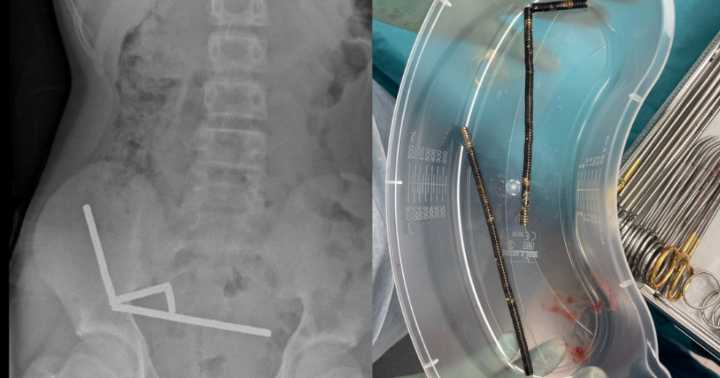

An X-ray shows lines of magnets in the boy's abdomen. New Zealand Medical Journal

The boy, who was not identified in the case report, ate between 80 and 100 magnets. The "high-power" magnets were 5x2 millimeters each, the report said.